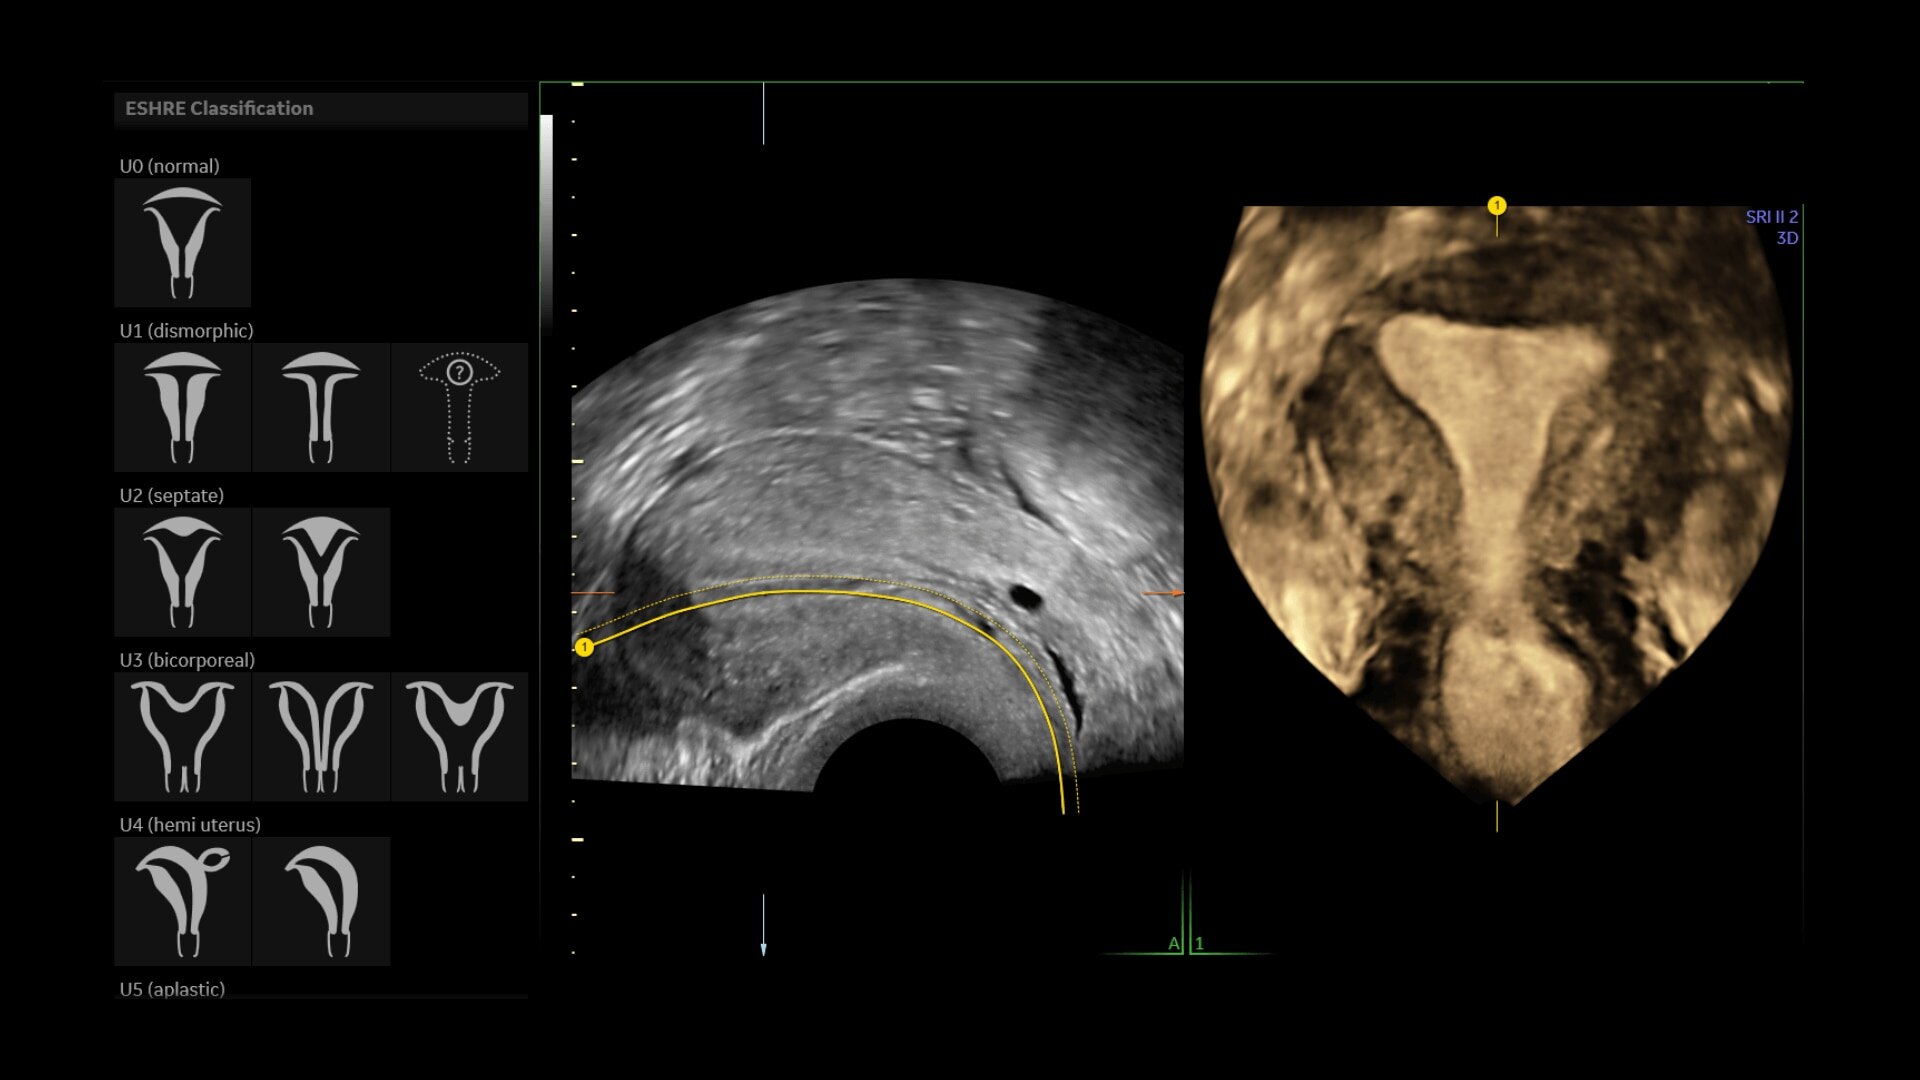

Uterine Trace

Easy display coronal view of uterus.

• Uterine Trace acquires the volume & then displays the coronal view of the uterus to simplify identification & reporting of uterine malformations.

• Uterine Trace acquires the volume and then displays the coronal view of the uterus linking to ASRM, ESHRE and ESGE Uterine Classification guidelines to simplify identification and reporting of uterine malformations